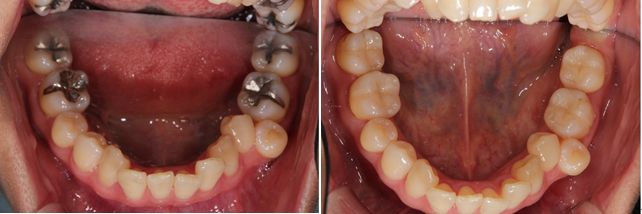

術前術後です。奥歯の銀歯が気になるとの患者様でしたが、このようにセラミックインレーに変更しましたが、大変喜ばれました。